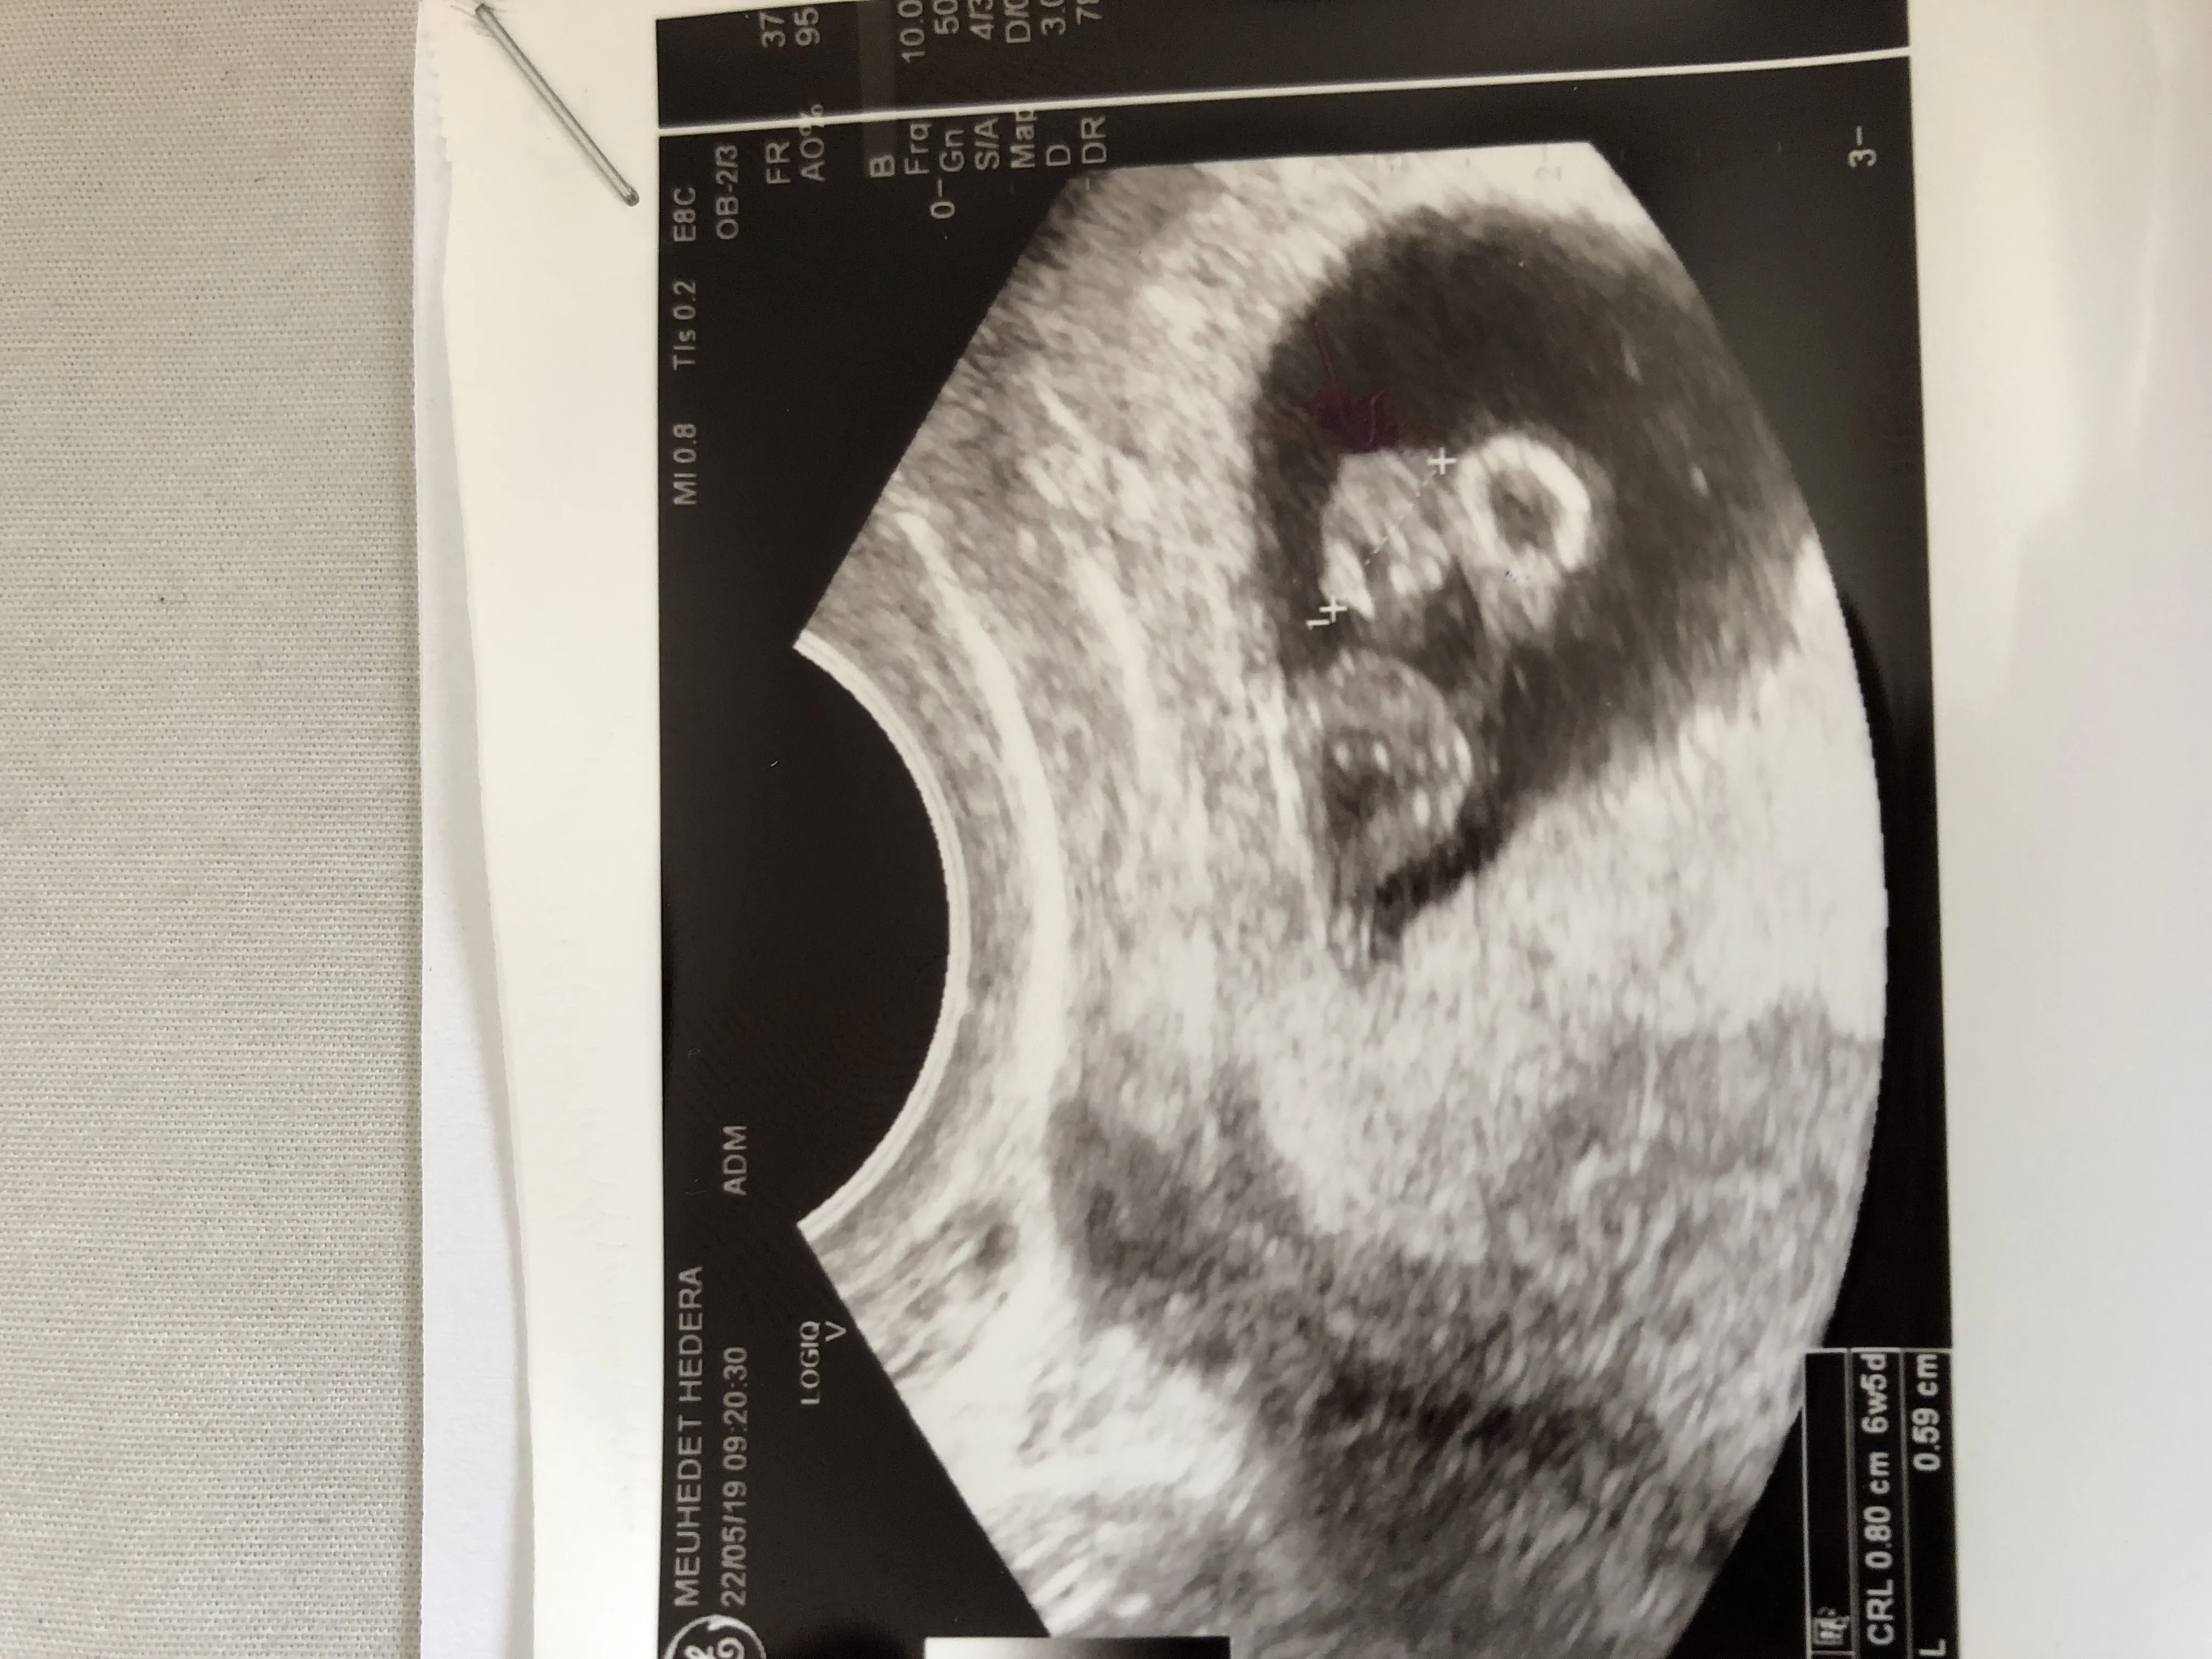

איך אני יודעת את הגיל שלו?

אני מניקה וקיבלתי מחזור לפני 4 חודשים

מאז לא היה כלום

לקחתי גלולות ובעקבות מליון דימומים הפסקתי גלולות

טבלתי ואני יודעת (99%) שהיום של המקווה זה היום שבו נכנסתי להיריון (לפני 4 שבועות)